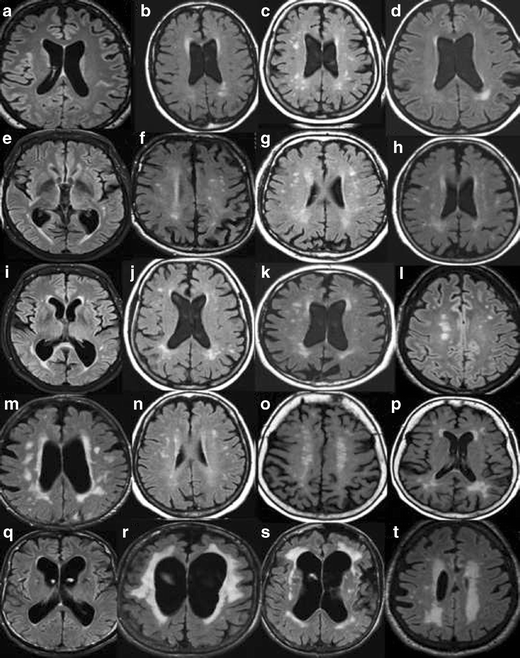

Fazekas grades. Fazekas степени мрт. Фазекас 2 мрт. Шкала Фазекас мрт. Лейкоареоз 3 степени по Fazekas.

Fazekas grades. Fazekas степени мрт. Фазекас 2 мрт. Шкала Фазекас мрт. Лейкоареоз 3 степени по Fazekas.

Fazekas grades. Классификация Фазекас. Fazekas мрт. Лейкоареоз степени по Fazekas. Фазекас классификация мрт.

Fazekas grades. Классификация Фазекас. Fazekas мрт. Лейкоареоз степени по Fazekas. Фазекас классификация мрт.

Fazekas grades. Фазекас классификация мрт. Лейкоареоз Fazekas 1 что это. Fazekas степени мрт. Лейкоареоз степени по Fazekas.

Fazekas grades. Фазекас классификация мрт. Лейкоареоз Fazekas 1 что это. Fazekas степени мрт. Лейкоареоз степени по Fazekas.

Fazekas grades. Фазекас 2. Fazekas 0. Фазекас 3.

Fazekas grades. Фазекас 2. Fazekas 0. Фазекас 3.